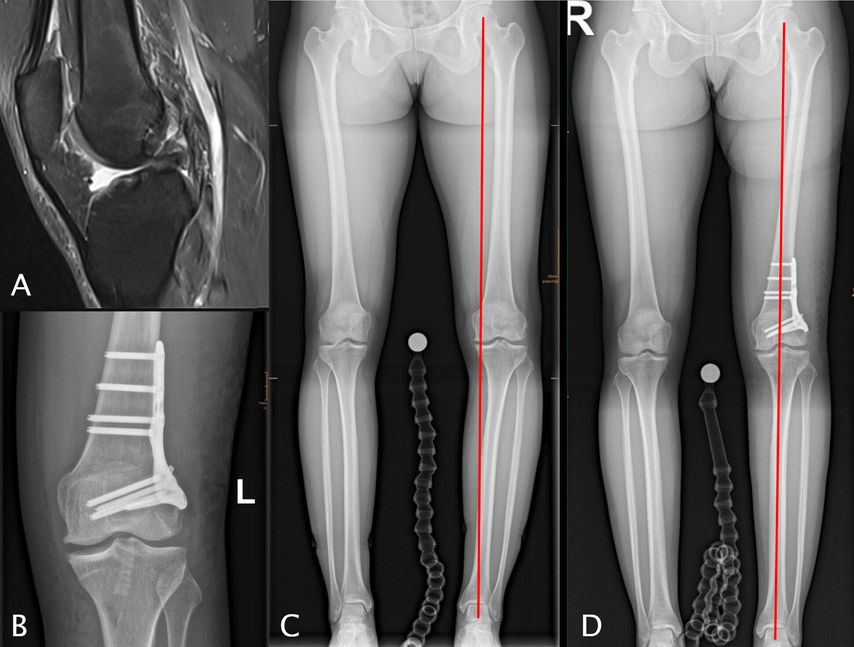

Abb. 1: 13-jähriger männlicher Fußballspieler mit VKB-Ruptur rechts (A), Valgusfehlstellung von 9° rechts aus dem distalen Femur (LDFA = 81°), proximaler Tibia (MPTA = 91°), Valgus von 5° Grad links primär aus dem distalen Femur (LDFA 84°) (C). Erfolgte Hemiepiphyseodese am medialen distalen Femur und an der medialen proximalen Tibia rechts sowie VKB-Plastik (4-Strang-Semitendinosus-Graft) (B). Korrekturerfolg vier Monate postoperativ (D)